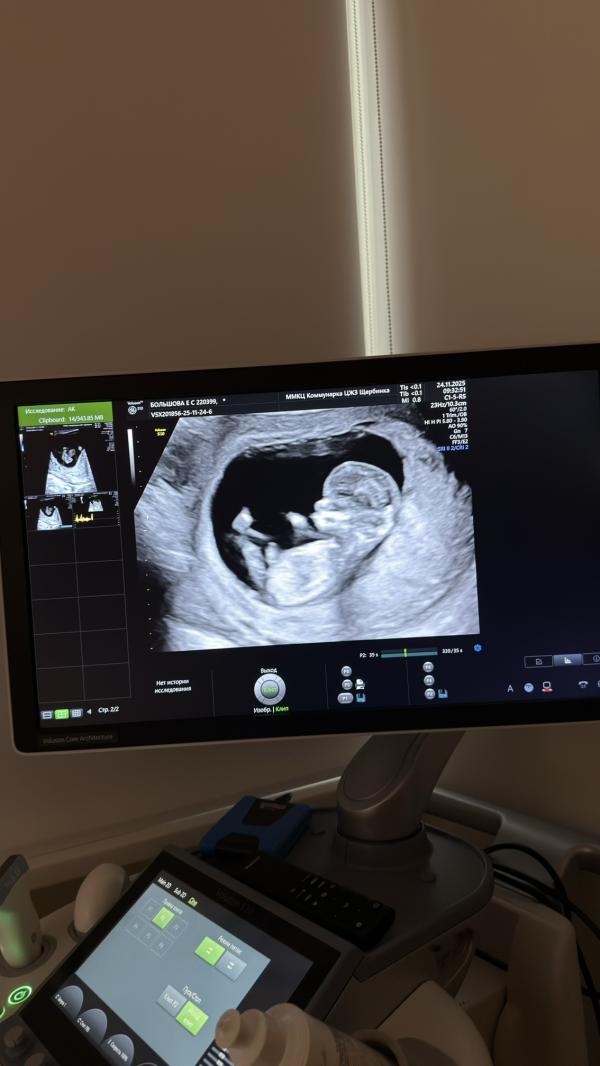

Сегодня был первый скрининг❤️🤰

Девочки, у кого совпадал пол с первым скринингом? Мне предположительно сказали, но думаю после второго скрининга сделаем гендр пати 🤭